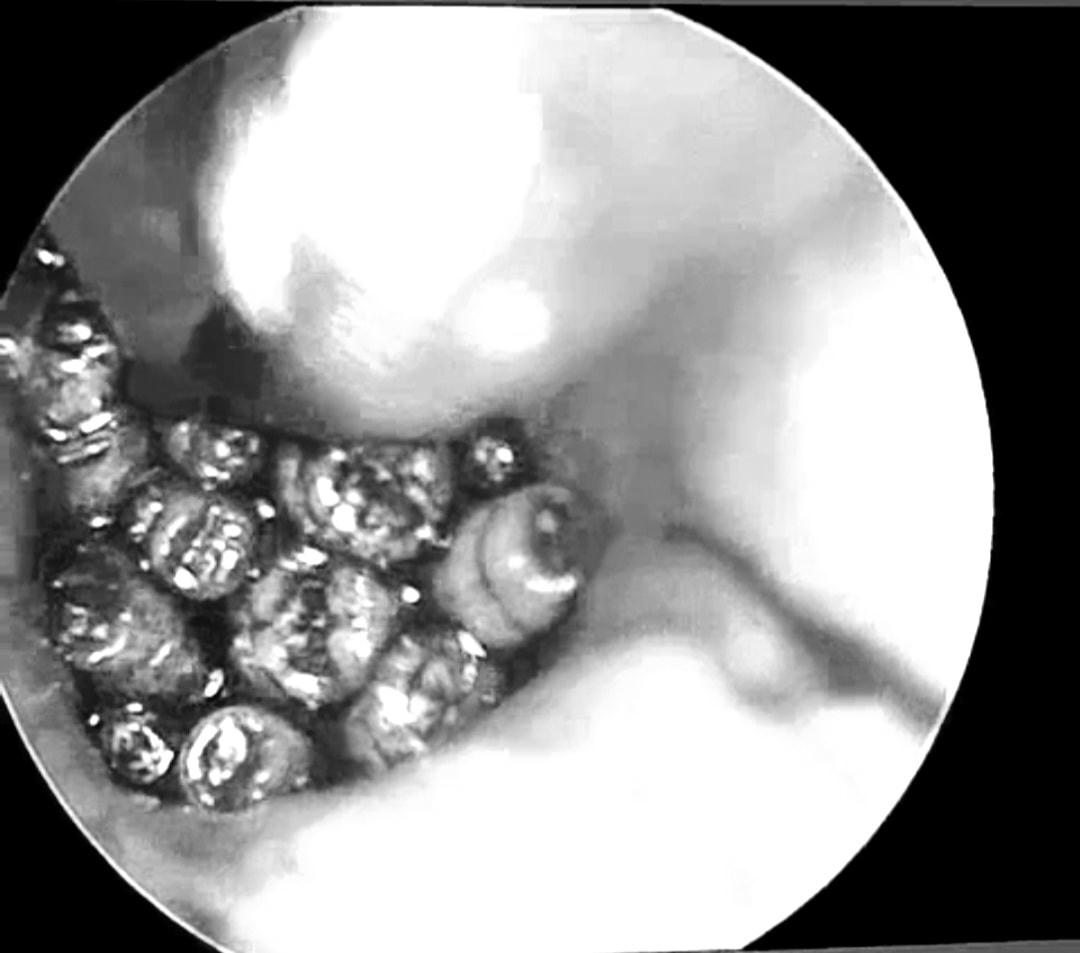

Hàng chục con giòi lấp đầy hòm nhĩ của một bệnh nhân

Tiến hành nội soi, các bác sĩ phát hiện ống tai của bệnh nhân Đ.H. hẹp, đọng nhiều máu tươi. Khi hút sạch máu, quan sát thấy dị vật màu trắng di động, nhiều hình ảnh giống con giòi lấp đầy hòm nhĩ, màng nhĩ thủng rộng.

Sau khi làm các xét nghiệm tiền phẫu, bệnh nhân được đưa vào khoa Phẫu thuật Gây mê hồi sức. Tại đây, các bác sĩ khoa Tai Mũi Họng tiến hành nội soi, gắp hàng chục con giòi sống trong tai giữa của bệnh nhân.